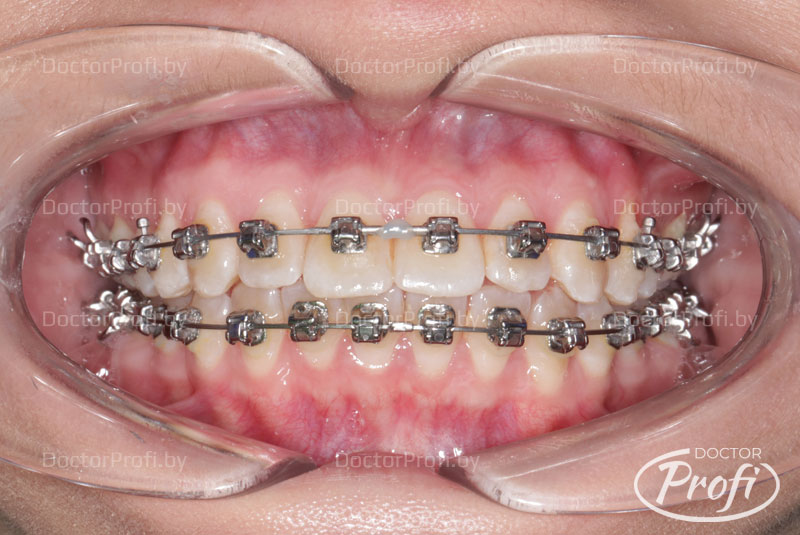

• Проведена коррекция прикуса.

• Улучшена форма зубных рядов и положение зубов.

• Ортодонтическое лечение проводилось брекет-системой Damon.

В результате проведенного лечения пациентка обрела красивую улыбку, правильный прикус, ровные и здоровые зубы.

После